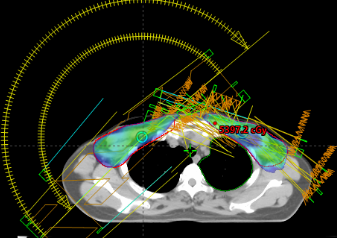

中信惠州医院肿瘤中心完成首例双侧乳腺癌放射治疗,此项技术的成功开展,标志着肿瘤中心对乳腺癌的精准治疗水平又上新的台阶。双侧乳腺癌由于解剖形态不规则,照射体积大,危及器官(肺、心脏,左前降支)受量不容易控制等诸多因素,计划设计难度大,复位要求更高。本次治疗在计划设计阶段,采用了双中心布野,评估了双拉弧,双调强野以及拉弧+IMRT衔接的治疗方式,最后综合考虑左臂无法充分上举的实际情况,最终采用左侧IMRT+右侧拉弧的放疗技术,肺、心脏,左前降支等危及器官限值均在要求范围内,处方剂量为5000cGY/200cGY,每次治疗前均实施CBCT进行位置校准。病人于2024年2月22日至2024年3月27日顺利完成放疗,无明显严重放射性皮肤反应。